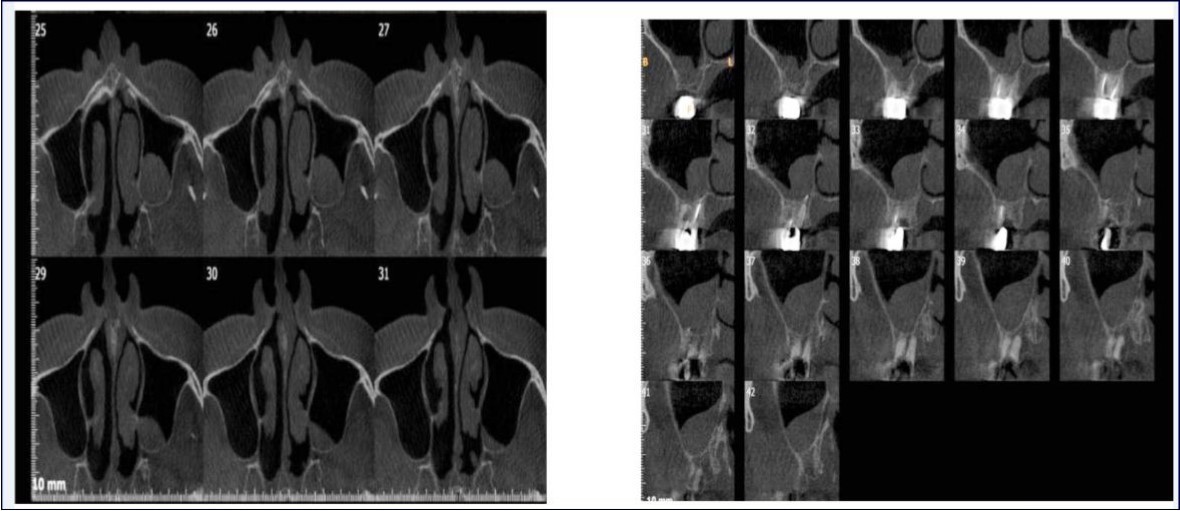

Sinus augmentation procedures were carried-out in 17 patients seeking implant options for oral rehabilitation including 10 for direct and 10 of indirect procedures (n=20, 10 direct and 10 indirect). The study comprised of 43% females and 57% males with a mean age of 46.07 years. A total of 17 patients (20 segments) satisfying the above criteria requiring placement of implants in atrophic maxilla/ increased pneumatisation of the maxillary sinus were selected for the study. The patients were informed about the study including the use of the synthetic graft material and their approval was sought before their inclusion in the study. A written informed consent was obtained from each of the participating patients. For each patient, a detailed case history was taken including chief complaint, history of presenting illness and medical history and personal history. A thorough clinical examination, including systemic and regional examination, was done. Patients with sinus pathology, previous sinus surgeries, chronic smokers, patients under 18 years of age, and with underlying systemic conditions which contradicts any surgical procedures were excluded from the study. The type of sinus lift was decided based on the pre-operative residual bone height evaluated radiographically. The residual bone height was recorded using CBCT scan and a computer based software where the measurements were made from the crest of the ridge till the sinus floor lining. Indirect sinus augmentation was done in patients with a bone height of <9mm but more than or equal to 5mm. Patients with a bone height of less than 5mm were taken up for direct sinus augmentation. The period of edentulousness varied from 6 months to 12 months. Apically tapered, commercially pure titanium implants (Life Care Devices Private Limited Mahim, West Mumbai, India) were used for patients undergoing indirect sinus augmentation. The length of implant was 8, 10, and 11.5 with diameters of 3.5, 4.0, and 5 mm respectively. Patients in the category of direct augmentation underwent the lateral approach procedure and augmentation with an alloplastic graft material. Implant placement was done after 6 months as the second stage procedure. The patients were assessed clinically at immediate post-operatively, and at 1 week, 1 month, 3 months, and 6 months post-operatively. Radiographic assessment for bone height was done pre-operatively and at 6 months post-operatively using cone beam computer tomography. In this comparative study, the measurements were tabulated and statistically analyzed to evaluate the difference in increase in bone height between direct and indirect sinus augmentation procedures radiographically. Orthopantomographs (screening tool) were taken to rule-out other pathologies and as a part of initial assessment. CBCT scans were assessed for pre-operative and post-operative bone height, bone width and bone density. The CBCT scans were obtained from Kodak 9300 which is a hybrid machine using a CS3D imaging software and flap panel detector sensor with exposure parameters of 90 KVp and 10 mA and resolution of 90 microns. The cross sections were made 1mm apart. (Image 1, Image 2, Image 3) The bone height measured pre-operatively using CBCT considered the pre-operative bone height as a measurement taken from the crest of the ridge till the sinus floor and post-operatively, from the crest till hyper-density evident apically. These measurements were standardized as a computer software drawing tool was used. Bone width was taken as the bucco-palatal width at three intervals- at the crest, 3mm from the crest and 6mm from the crest. Bone density was assessed visually by the width of trabecular pattern and were classified based on Misch‘s classification.4 Another additional bone density tool used was the pixel values (the gray scale values) obtained on the CBCT scan, although not reliable, and comparison done pre-operatively and post-operatively. The pixel values contained were a mean of three measurements obtained along the residual bone corresponding with the bone width levels.

Image 3.Axial sections of CBCT showing sinus mucosal thickening